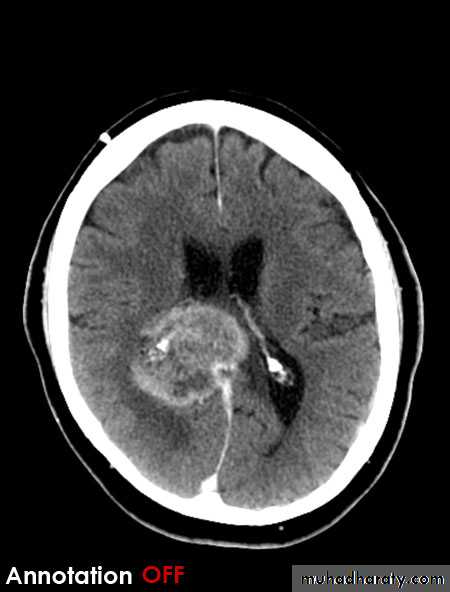

Posterior fosse tumor

Medullo blastoma

Age incidence between 5-15 Y represent about 35-40 %of PFT

Arise from the midline mainly within or from the roof of the 4 TH ventricle fill the fourth ventricle & seeding via the csf so can seen in the distal part of the spinal canal .

CT finding as well circumscribed lesion heterogeneous in density ,have solid & cystic part , with also scattered calcification little surrounded edema , the solid part is enhance

90 % present with obstructive hydrocephalous at the level of the 4Th V. with dilatation of the lateral V. ( body , frontal , temporal & third ventricle )

40 % of child have secondary metastasis at the time of presentation